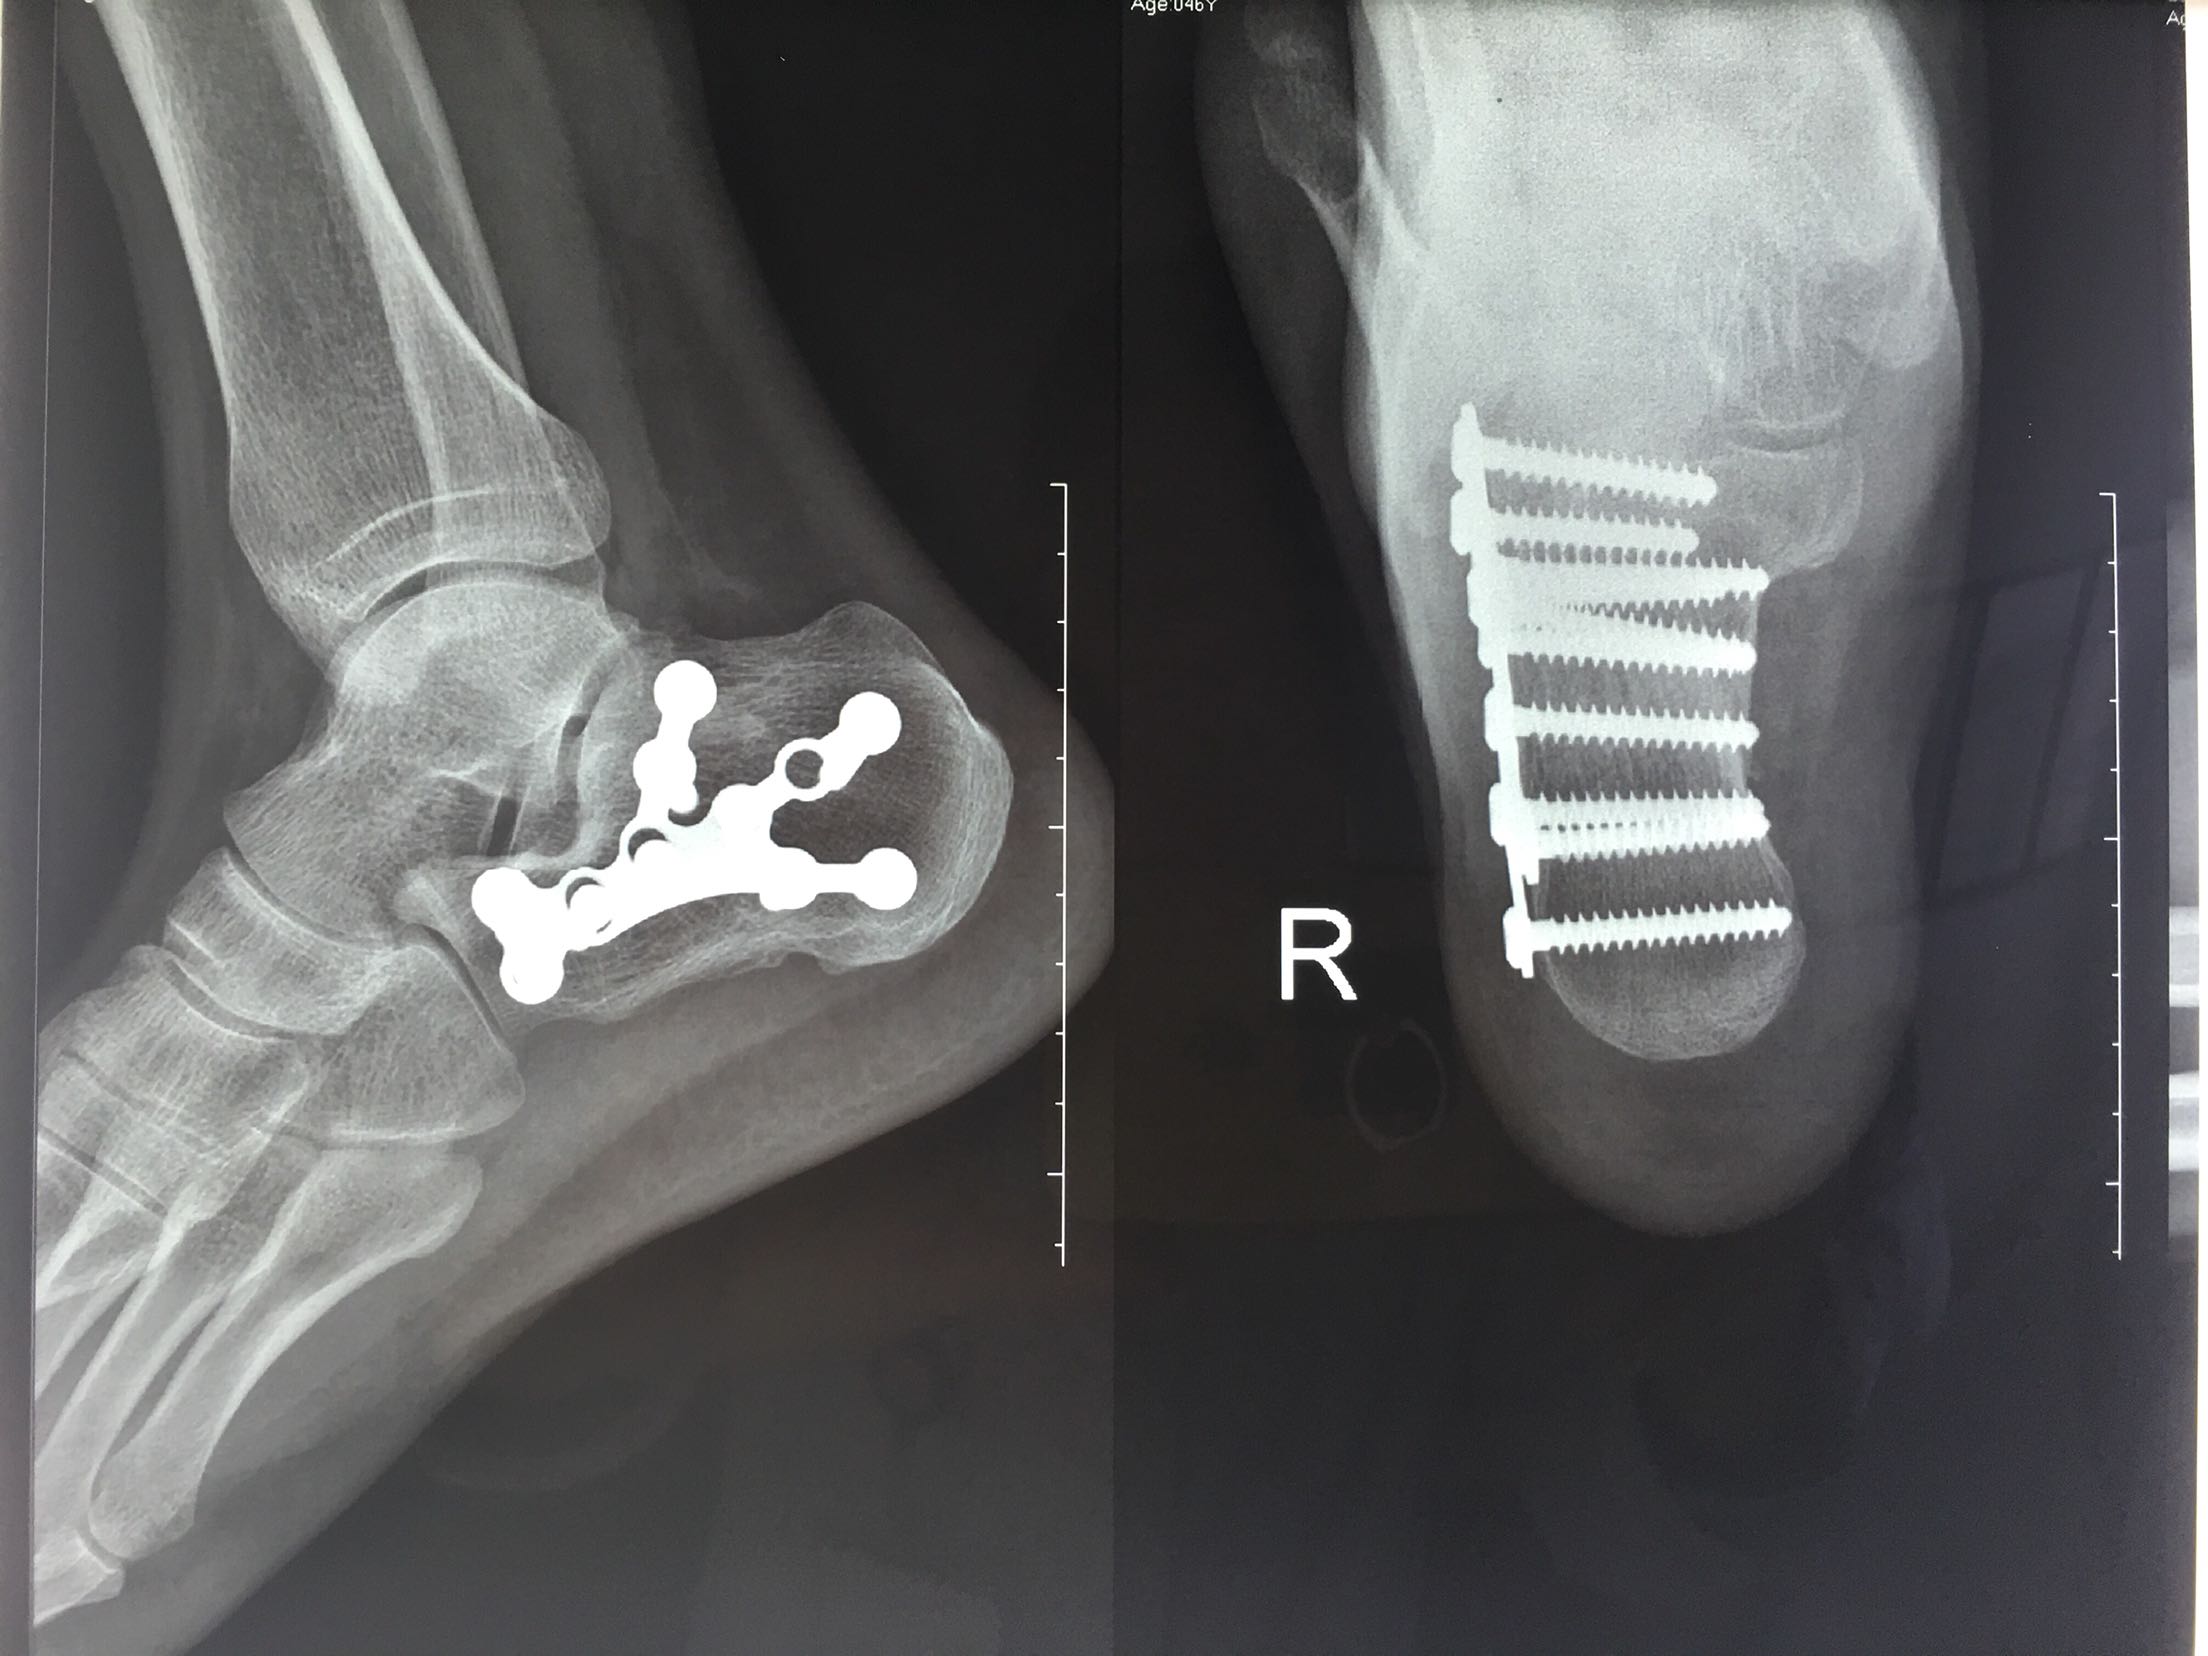

跟骨骨折